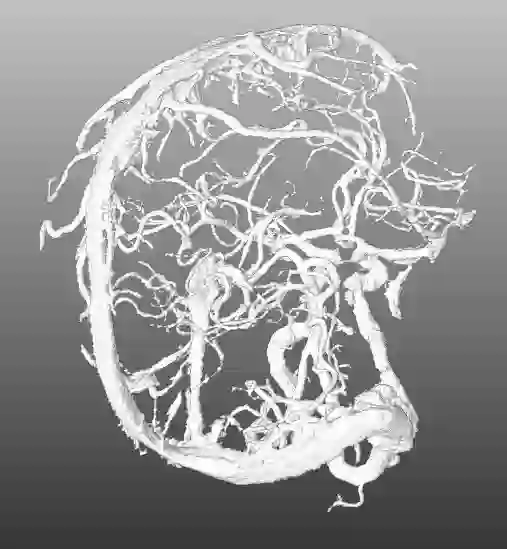

During the diagnosis of ischemic strokes, the Circle of Willis and its surrounding vessels are the arteries of interest. Their visualization in case of an acute stroke is often enabled by Computed Tomography Angiography (CTA). Still, the identification and analysis of the cerebral arteries remain time consuming in such scans due to a large number of peripheral vessels which may disturb the visual impression. In previous work we proposed VirtualDSA++, an algorithm designed to segment and label the cerebrovascular tree on CTA scans. Especially with stroke patients, labeling is a delicate procedure, as in the worst case whole hemispheres may not be present due to impeded perfusion. Hence, we extended the labeling mechanism for the cerebral arteries to identify occluded vessels. In the work at hand, we place the algorithm in a clinical context by evaluating the labeling and occlusion detection on stroke patients, where we have achieved labeling sensitivities comparable to other works between 92\,\% and 95\,\%. To the best of our knowledge, ours is the first work to address labeling and occlusion detection at once, whereby a sensitivity of 67\,\% and a specificity of 81\,\% were obtained for the latter. VirtualDSA++ also automatically segments and models the intracranial system, which we further used in a deep learning driven follow up work. We present the generic concept of iterative systematic search for pathways on all nodes of said model, which enables new interactive features. Exemplary, we derive in detail, firstly, the interactive planning of vascular interventions like the mechanical thrombectomy and secondly, the interactive suppression of vessel structures that are not of interest in diagnosing strokes (like veins). We discuss both features as well as further possibilities emerging from the proposed concept.